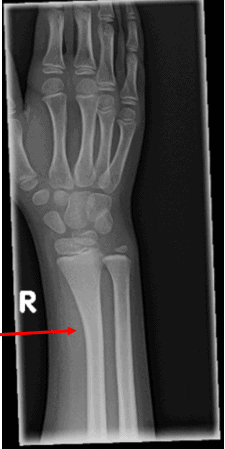

This patient sustained a bowing fracture of the radius. The x-ray shows abnormal gentle bowing of the radial shaft without any definite fracture line or cortical break, as well as soft tissue swelling.

- Bowing fractures of the long bones occur exclusively in children and adolescents

- Radius and ulna are the most common sites, followed by the fibula

- Because they’re softer, more elastic, and have thinner cortex, pediatric bones tend to bend under angulated longitudinal force/stress. With low force, the bones bend and return to normal shape and position upon release of the force. If the force is greater than the mechanical strength of the bone, the bone undergoes a plastic deformation and remains deformed and bowed upon release of the force. Pathologically these bowed bones have multiple micro fractures along the concave border of the bone which are not visible on radiographs